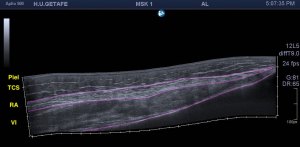

Cuando hacemos una Ecografía para descartar una tendinopatía, lo primero que tenemos que conocer es la normalidad.

El tendón ecográficamente es por definición hiperecogénico. Bajo esta premisa, sí yo observo un tendón hipoecogénico tengo que empezar a sospechar.

1. Anisotropía que ya sabemos que es el cambio en la ecogenicidad del tendón debido al ángulo de insonación o la colocación de la sonda.

Angulando lo más paralelo al tendón posible. Sí es necesario taloneamos la sonda con nuestra mano.

Estirando el tendón siempre para explorarlo correctamente. Posicionamos al paciente para esto.

Otra cuestión que nos hace sospechar tendinopatía es el aumento de tamaño del tendón. Esto lo podemos valorar mediante una exploración comparativa con el lado sano.

Si aparece dolor local siempre será un punto a favor para nuestro estudio y tener la certeza de que los hallazgos enlazan con la clínica.

En resumen, tendremos tendinopatía sin hallemos:

Hipoecogenicidad

Aumento de tamaño

Tendinopatía Aquiles. Aumento de tamaño e hipececogenidad

Tendinopatía rotuliana. Aumento de grosor e hipecogenicidad.